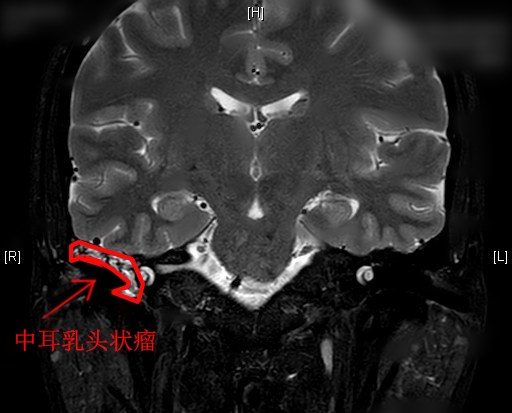

清华长庚耳鼻咽喉头颈外科成功诊治一例罕见中耳乳头状瘤

北京清华长庚医院5月31日电(耳鼻咽喉头颈外科供稿)  近日, 清华大学附属北京清华长庚医院耳鼻咽喉头颈外科成功诊治了一例中耳乳头状瘤病例,患者已康复出院。该病为罕见病,目前据文献报道仅10余例。

结合患者入院后完善的检查,伊海金多次组织病例讨论,高度怀疑患者所患的为中耳乳头状瘤,该病早期症状不典型,常常表现为耳闷、听力下降等,“这种肿瘤原发于中耳者非常罕见,它属于良性肿瘤,但原发于中耳的病变恶变率较高,需要及时治疗。”伊海金说。